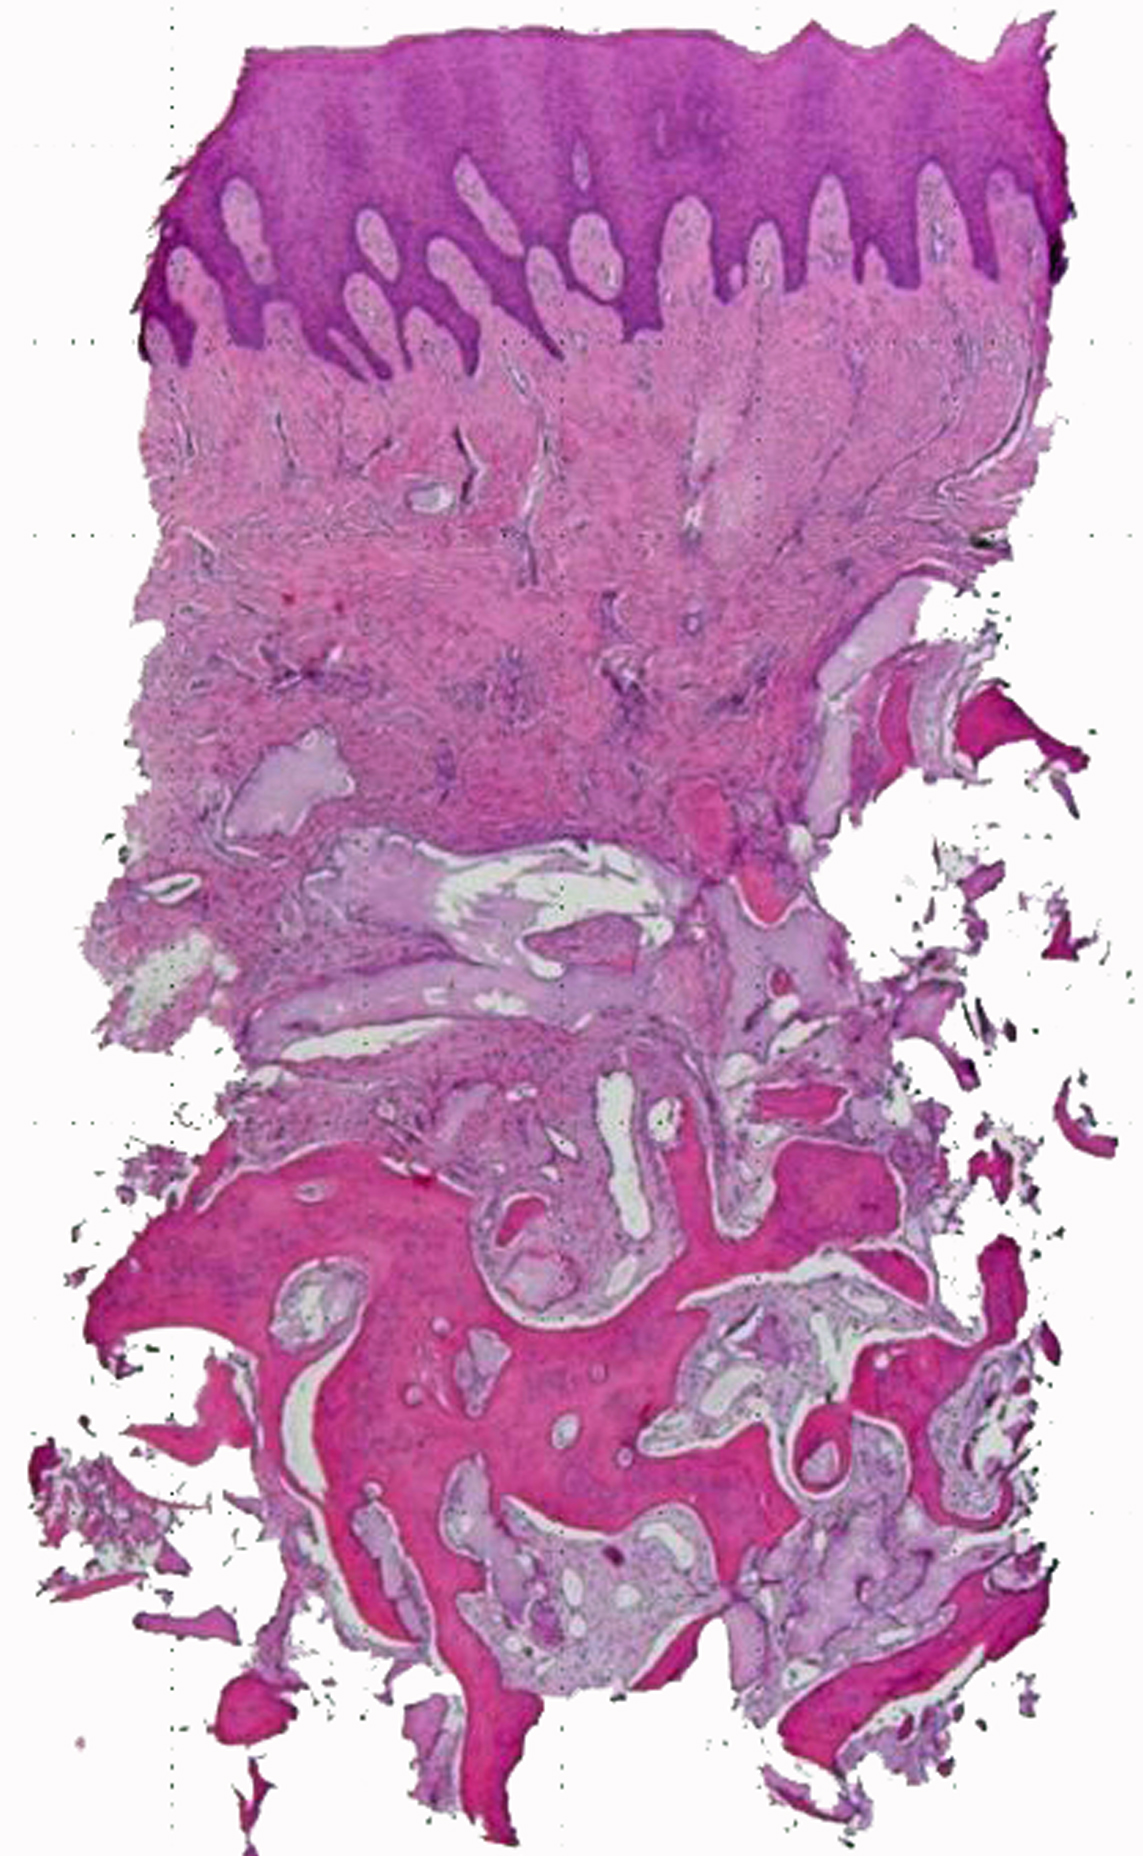

Di recente l’Autore ha pubblicato una ricerca clinica con prelievi istologici su otto casi di ridge preservation (25). Sono stati prelevati campioni osseo-connettivali che sono stati refertati dal Patologo dr. Paolo Spina del reparto di Patologia dell’Ospedale Cantonale di Locarno (CH).

I referti istologici sono stati simili in tutti i campioni esaminati: materiale costituito da mucosa squamocellulare senza atipie significative, con sottostante tessuto connettivo con moderata fibrosi, interposto con tessuto stromale comprensivo di vasi capillari e tessuto osseo con apposizione di lamelle di matrice osteoide comprendenti occasionali osteoblasti (attribuibili probabilmente a tessuto osseo neoformato) adiacenti a tessuto osseo mineralizzato (attribuibili a osso nativo ) (Figura 2).

Anche se si tratta di una coorte piccola, l’uniformità dei risultati istologici e la valutazione di “osso neoformato” e “osso nativo” , cioè tessuto osseo con un grado di maturazione non distinguibile dall’osso nativo del paziente, sono indicative della prevedibilità rigenerativa della tecnica Fill & Seal.